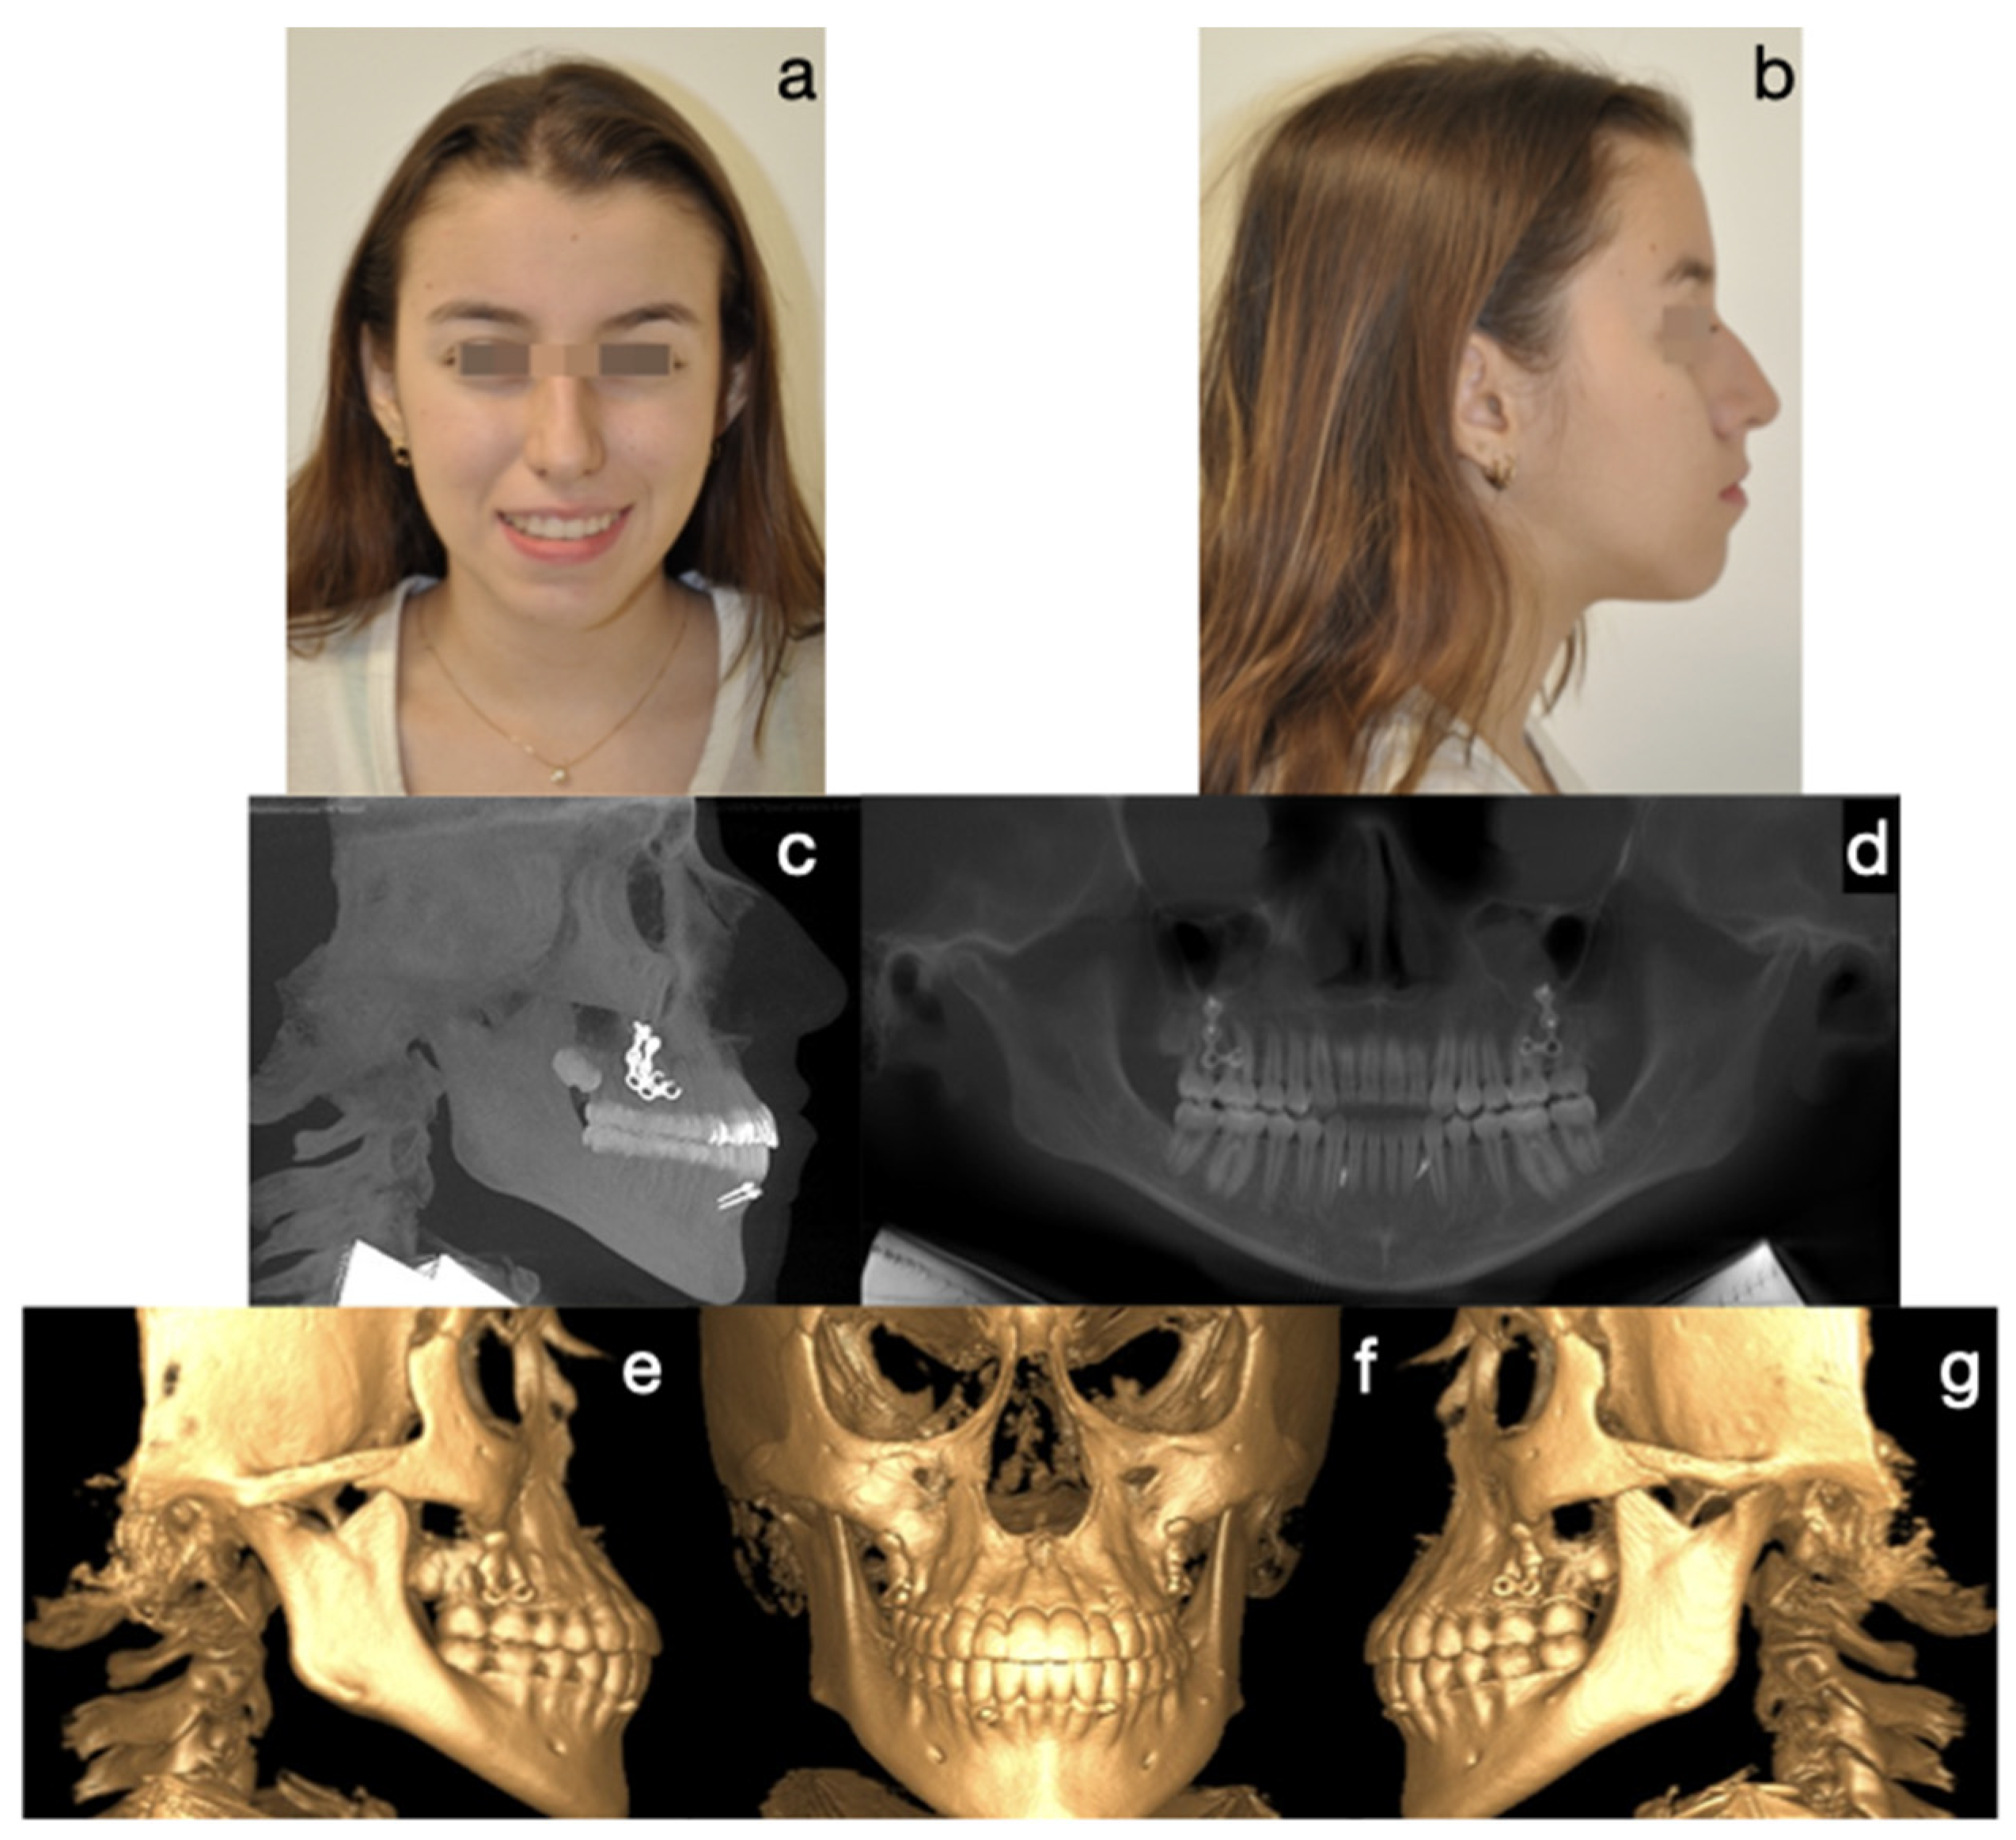

- Protocol B: Bilateral condylectomy and orthognathic surgery performed in one session, followed by post-surgical orthodontics. The surgery order is first the high Le Fort I osteotomy in bilateral step, then the bilateral condylectomies, and then the sagittal osteotomies of the bilateral mandibular ramus, ending with advancement mentoplasty when necessary. This approach is suitable for patients with no growth potential, severe skeletal issues, aberrant malocclusions, and significant psychoemotional distress due to facial appearance. It is indicated for those needing rapid correction to improve their quality of life (Figure 5 and Figure 6).

| 4 | 30 | M | Severe mandibular prognathism. Elongated condyles. Accelerated mandibular growth from the age of 15 years and beyond the age of 20 years. Negative overjet of 12 mm. No family history of Class III. Failed orthodontic treatment. | Positive report for uptake ratio above normal values in condyles, with respect to clivus. Did not provide value | Right condyle: 6 mm Left condyle: 6 mm | Increased thickness of the layers of the soft condyle, without giving thickness value. Increased proliferation of hypertrophic chondrocytes on medullary bone. Positive findings for BCH. | Type B. Bilateral condylectomy, bimaxillary orthognathic surgery and mentoplasty all in the same surgical time. | 60 months |

| 5 | 17 | M | Severe mandibular prognathism. Elongated condyles. Accelerated mandibular growth since the age of 14 years. Negative overjet of 16 mm. No family history of Class III. Failed orthopedic treatments. Depressive mood episodes. | Positive report for uptake ratio above normal values in condyles, with respect to clivus. Did not provide value | Right condyle: 6 mm Left condyle: 6 mm | Increased thickness of the layers of the soft condyle, without giving thickness value. Increased proliferation of hypertrophic chondrocytes on medullary bone. Positive findings for BCH. | Type B. Bilateral condylectomy, bimaxillary orthognathic surgery and mentoplasty all in the same surgical time. | 60 months |